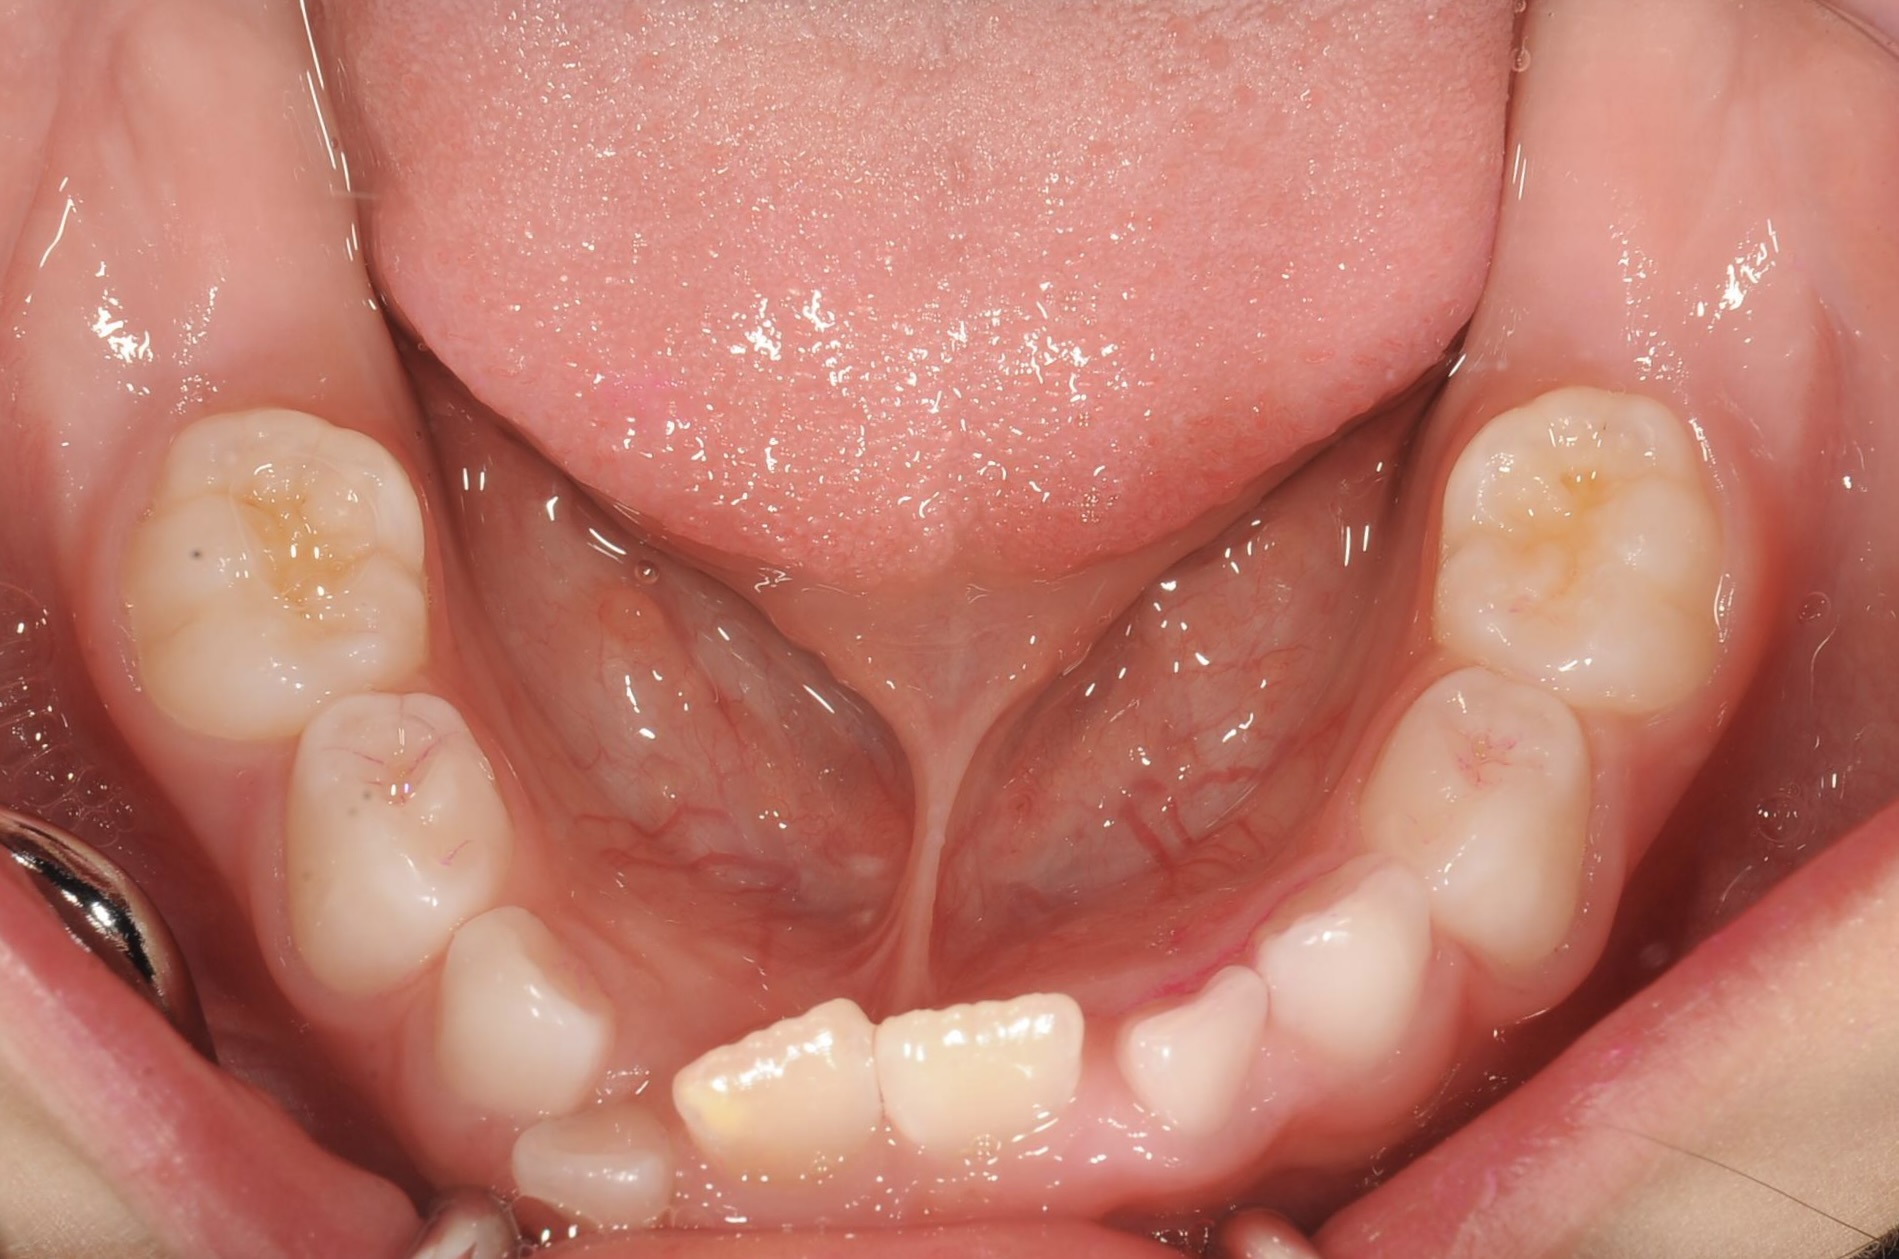

BEFORE

5歳 女児 小児矯正

歯並びの状態:

叢生(ガタガタ)

過蓋咬合(咬み合わせが深い)

主訴

右下の歯が飛び出ているので治したい。

診断名・主な症状

過蓋咬合

年齢

5歳

治療内容

上下の歯並びの幅を拡げつつ、前歯の関係を改善しました。